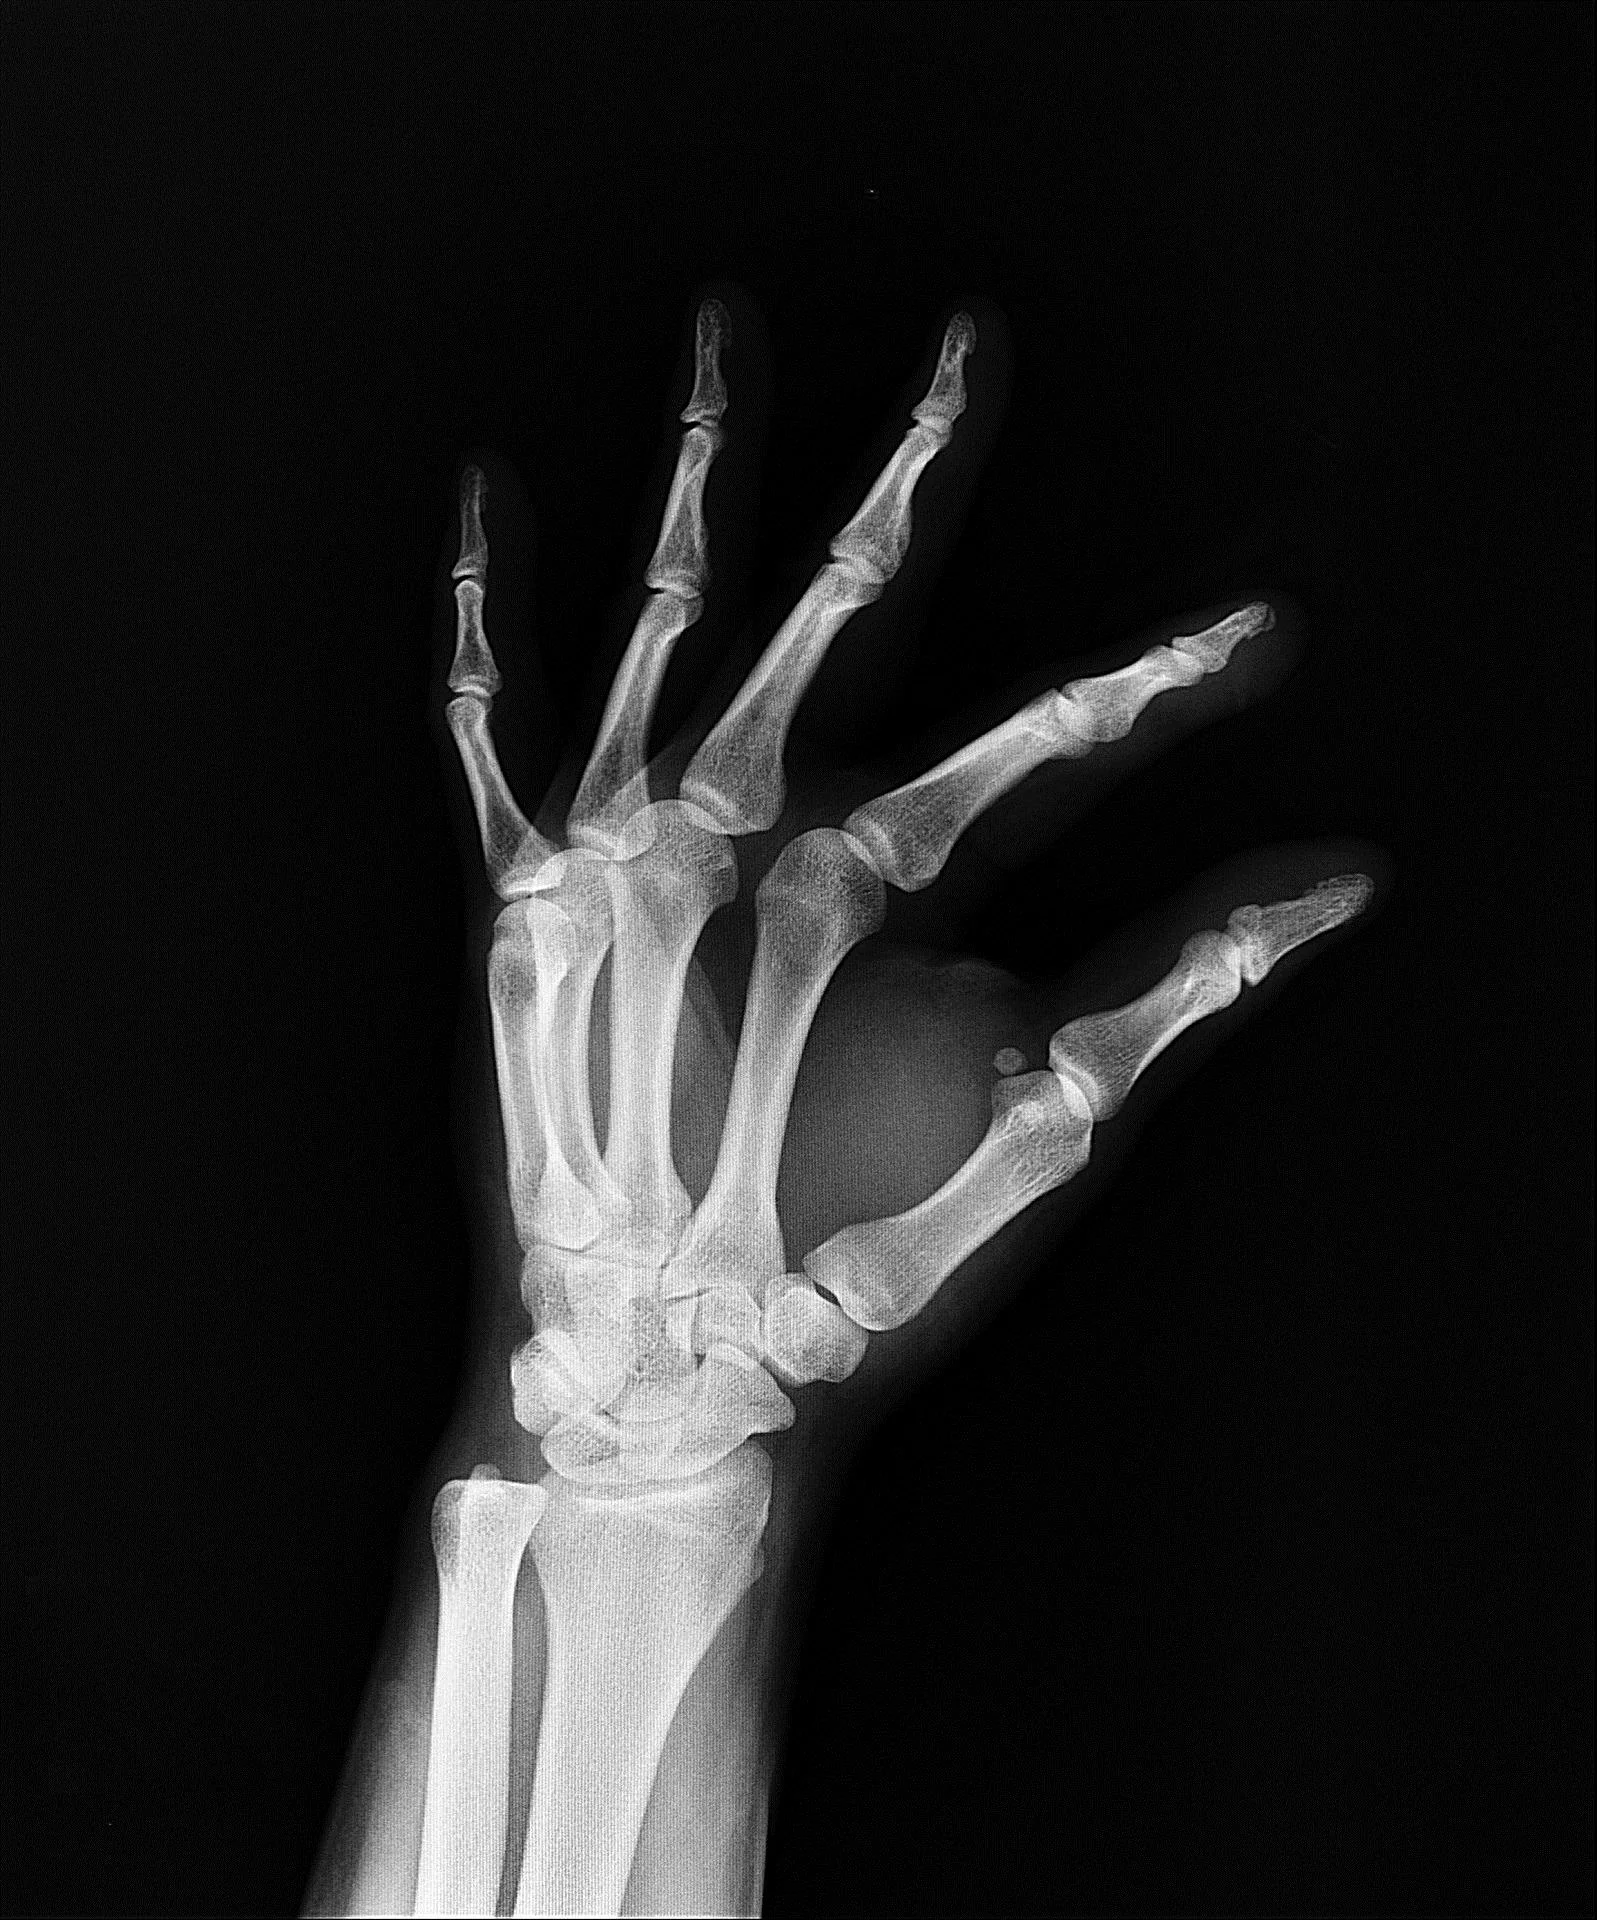

Osteoarthritis is a common condition that affects joints of the body. It causes structural changes within a joint or multiple joints, resulting in pain and loss of function. Osteoarthritis is associated with a number of factors, including genetic, mechanical, hormonal and inflammatory factors, and is not just a disease of aging or an ‘older persons’ disease.